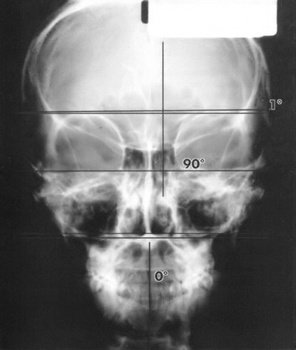

Рентгеновский снимок, сделанный перед сеансом Квантового Прикосновения для черепа и шейных позвонков. Заметьте, что второй позвонок отклонен на 8 градусов в направлении левого носового отверстия.

Рентгеновский снимок, сделанный после сеанса Квантового Прикосновения для черепа и шейных позвонков. Заметьте, что теперь второй позвонок расположен вертикально.